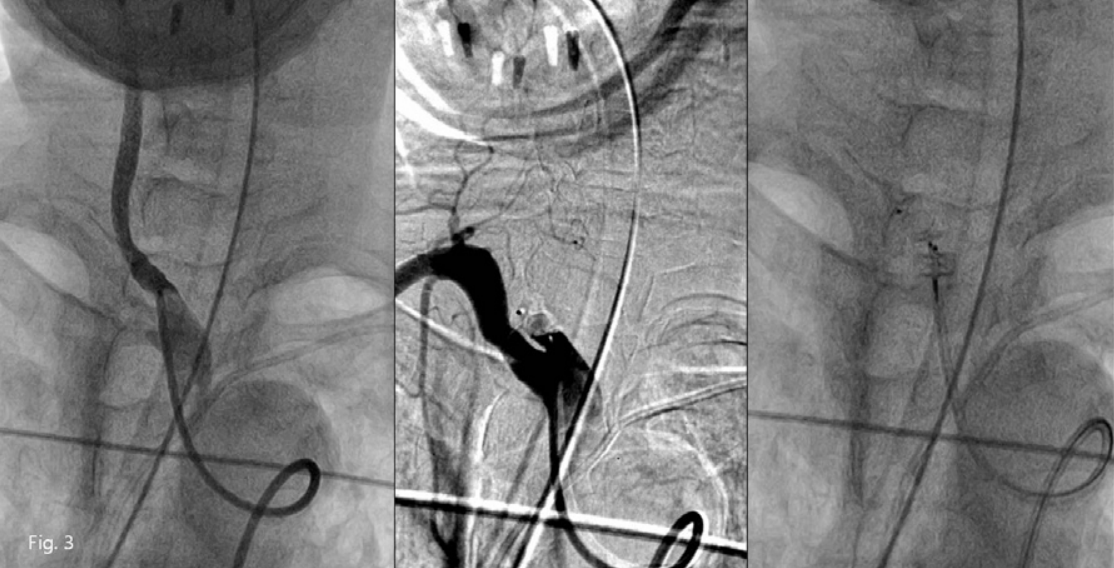

Fig. 2

A. Contrast enhanced axial CT scans show suspicious focal fistula from the upper medial wall of right proximal common carotid artery to the tracheostomy lumen (arrow).

B. Coronal reformatted CT image right innominate ar teriography show focal bulging of the upper medial wall of right proximal common carotid artery and contrast leakage into tracheostomy site (arrows).